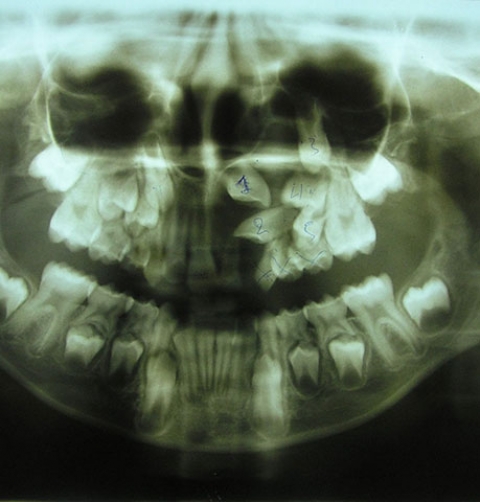

Στο ιατρείο του χρησιμοποιούνται όλες οι σύγχρονες τεχνικές της ορθοδοντικής, προς όλες τις ηλικίες και με όλα τα είδη μηχανισμών, όπως εξωτερικά και εσωτερικά άγκιστρα (brackets), μεταλλικά και διαφανή, κινητοί μηχανισμοί (μασκάκια).

Οι σύγχρονες τεχνικές μέθοδοι, σε συνδυασμό με την αδιάλειπτη επιστημονική ενημέρωση και την πολυετή εμπειρία του ιατρού, τον καθιστούν δικαίως πρωτοπόρο, αφού έχει αγγίξει τον ύψιστο στόχο του να μην παραπέμψει, έως και σήμερα, κανένα περιστατικό ασθενούς σε χειρουργική επέμβαση (ορθογναθικά περιστατικά).

Χωρίς Εξαγωγές

Εξαλείφοντας την ανάγκη εξαγωγής μόνιμων δοντιών, προσδίδει στις θεραπείες του το ύψιστο της απόδοσης και της αναλγησίας, με χρονικό όριο από 12 έως και 15 μήνες, κάνοντας την αναμονή του αποτελέσματος μια ευχάριστη και ξεκούραστη προσμονή.